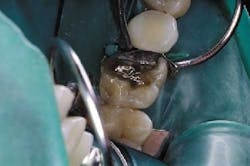

- Amalgam to be replaced.

A direct composite restoration on No. 30 can be seen in Fig. 3.